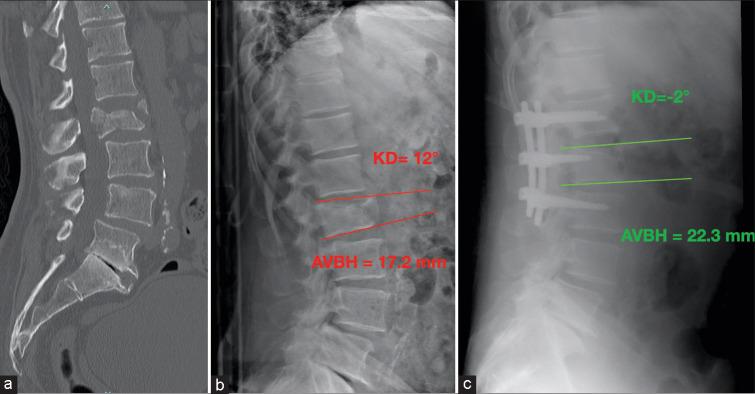

This retrospective case-control multicenter analysis involved patients with A3 and A4 vertebral fractures at the thoracolumbar junction (T11-L2) who underwent surgical treatment with either SSPF or SSOFIFL in the participating centers. Clinical outcomes were measured using the Oswestry Disability Index and visual analogue scale (VAS) both pre- and postoperatively. Radiological outcomes included kyphotic deformity (KD), anterior vertebral body height (AVBH), segmental kyphosis, and sagittal alignment parameters.

A total of 156 patients were enrolled in the study, with 81 patients in Group A (SSPF) and 75 patients in Group B (SSOFIFL). Group B demonstrated better correction of KD (Group B: 3.4 ± 2.7° vs. Group A: 8.3 ± 3.2°, = 0.003), AVBH, and sagittal alignment. A minor loss of correction was observed in Group B with respect to Group A (0.9 ± 1.7° vs 4.3° ± 2.1°, = 0.043). Blood losses were lower in Group A (78 ± 15 min vs. 118 ± 23 min, = 0.021) as well as during surgery (121.3 ± 34 mL vs. 210.2 ± 52 mL, = 0.031), but the post-operative hemoglobin levels were comparable between the two groups.

本研究共纳入156例患者,A组(SSPF)81例,B组(SSOFIFL)75例。B组在KD矫正方面表现更好(B组:3.4±2.7° vs. A组:8.3±3.2°,P = 0.003),AVBH和矢状面排列也更好。与A组相比,B组观察到轻微的矫正丢失(0.9±1.7° vs 4.3°±2.1°,P = 0.043)。A组的手术时间(78±15分钟 vs. 118±23分钟,P = 0.021)以及术中失血量(121.3±34毫升 vs. 210.2±52毫升,P = 0.031)较低,但两组术后血红蛋白水平相当。